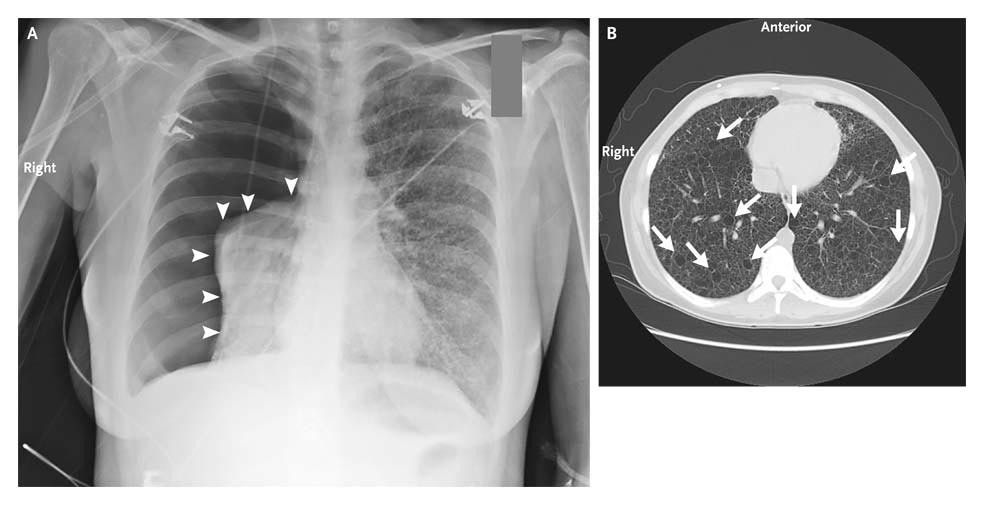

Q.69. A 30-year-old man presents with shortness of breath after a blunt injury to his chest, his RR is 30 breaths/min. CXR showed complete collapse of the left lung with pneumothorax, mediastinum was shifted to the right. The treatment of choice is?

Correct Answer : A

A chest tube is the most appropriate treatment for pneumothorax caused by trauma. It drains air or fluid from the chest cavity, allowing the lung to re-expand. This is the standard care for significant pneumothorax.